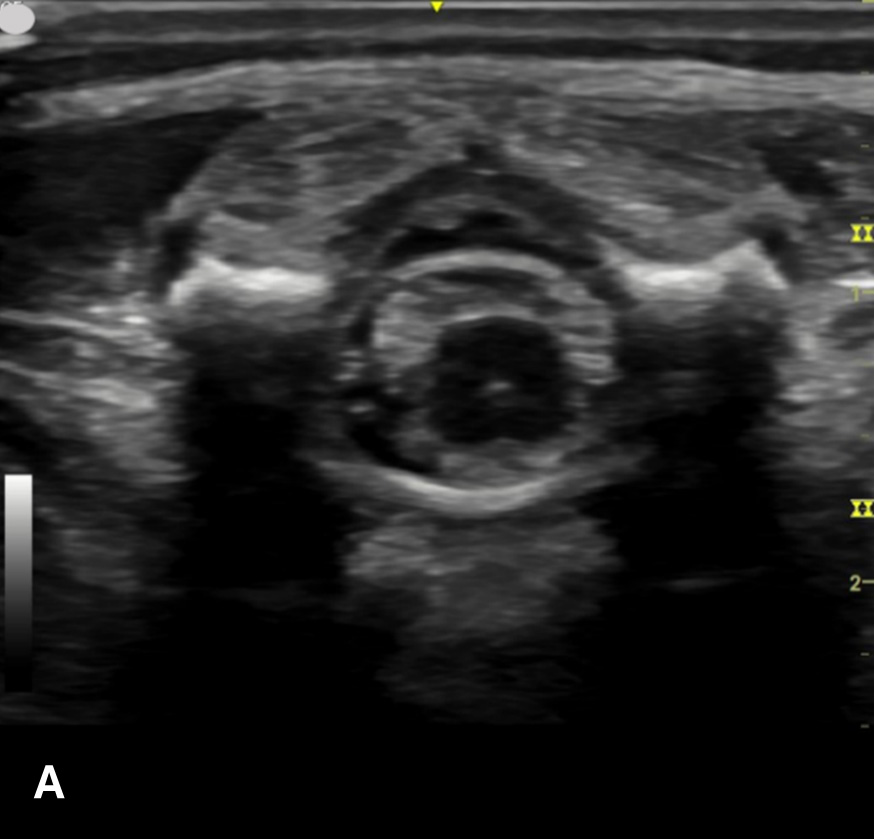

The transverse view should also be obtained to verify landmarks and identify any overlying vessels or hematomas (from prior attempts) to avoid. The transducer is rotated to the transverse position on the lower back and moved caudally over the spinous processes to locate the CM, which is a hypoechoic structure positioned in the center of the spinal canal. At higher levels of the CM, the ventral roots and dorsal roots can be identified, which are surrounded by the anechoic CSF. Next, gradually move the transducer caudally and observe the CM decreasing in size while being encircled by the hyperechoic fibers of the CE. (Figure 2) Once this sonographic landmark is identified, locate the center of the transducer and mark the corresponding area on the skin, aligning it with the center of the spinal cord. Subsequently, draw lines from both markers in both planes and utilize the point of intersection as a guide for inserting the LP needle. To enhance visualization of the spinal cord’s vascular supply, and avoid a space with any overlying vessels that may cause a traumatic tap, it is advisable to apply color Doppler in both the sagittal/longitudinal and transverse views.9 (Figure 3)

Figure 2 - Corresponding US image showing spinal canal structures in transverse view:

Figure 2 - Corresponding US image showing spinal canal structures in transverse view. 2A-B: The caudal portion of the transverse view shows DR (dorsal roots), VR (ventral roots), CSF (cerebrospinal fluid), and CM (conus medullaris). 2C-D: The probe is moved caudally demonstrating the tapered CM (orange dotted circle), CE (cauda equina, hyperechoic structure surrounding the CM) and a pocket of CSF. 2E-F: Demonstrate the disappearance of the CM, and the pocket of CSF becoming larger as the probe was moved caudally. The blue circle is the entire dural sac encircling the spinal canal.